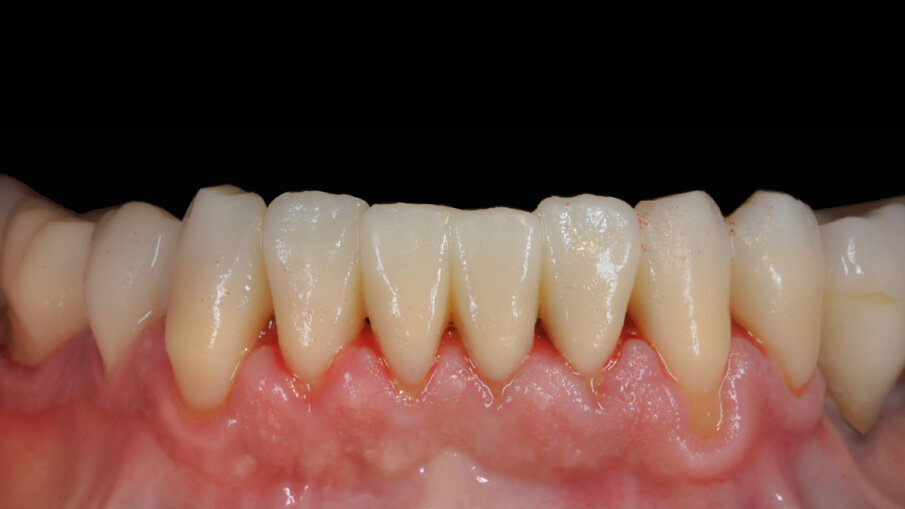

In odontoiatria, la TSLA viene utilizzata nella stampante Dfab, con cartucce a gradiente di colore Photoshade (DWS). Il processo inizia caricando il file .stl nel software Photoshade, che posiziona e supporta correttamente il restauro per ottenere precisione e adattamento ottimali. Si seleziona la gradazione Photoshade desiderata e si posizionano i limiti cromatici cervicali e incisali. Una volta approvato l’aspetto visivo del restauro, inizia il processo di stampa. La cartuccia Dfab monouso viene caricata nella parte superiore della stampante insieme al supporto di stampa con una piattaforma monouso. La parte superiore della Dfab viene chiusa e la cartuccia inclinata a 45 gradi. La stampa viene avviata dal software Photoshade Pro, con un flusso continuo di materiale mantenuto dalla gravità e da una pompa peristaltica silenziosa. Il raggio laser UV blu polimerizza selettivamente il composito, creando l’oggetto strato per strato. Completato l’oggetto, la Dfab viene aperta e la piattaforma di costruzione riportata in posizione orizzontale. Per rimuovere i residui di composito non polimerizzato, la piattaforma contenente i restauri viene lavata per 1-2 minuti in uno shaker con alcol etilico al 95%. I restauri vengono quindi separati manualmente dalla piattaforma, rompendo i supporti sottili con un movimento rotatorio. Eventuali ulteriori piccoli residui di composito non polimerizzato vengono rimossi con un pennello piatto immerso in alcol etilico al 95%. Infine, viene eseguita la post-polimerizzazione con un dispositivo a doppia energia (luce ultravioletta e calore) (Dcure, DWS), con un ciclo automatico di circa nove minuti (Figg. 4, 5).

Il paziente è seguito regolarmente con controlli semestrali e sedute di igiene per mantenere la salute orale ed evitare carie secondaria e problemi parodontali. Manifesta piena soddisfazione per il trattamento ricevuto e rimane collaborativo. Nell’ultima visita, i restauri in composito ibrido Irix si presentano integri e funzionali. È necessaria solo una nuova lucidatura, eseguita dopo la seduta di igiene orale con la tecnica di lucidatura moderna appena descritta. Il paziente sarà monitorato e prevediamo di documentare il follow-up a medio e lungo termine (Fig. 7).